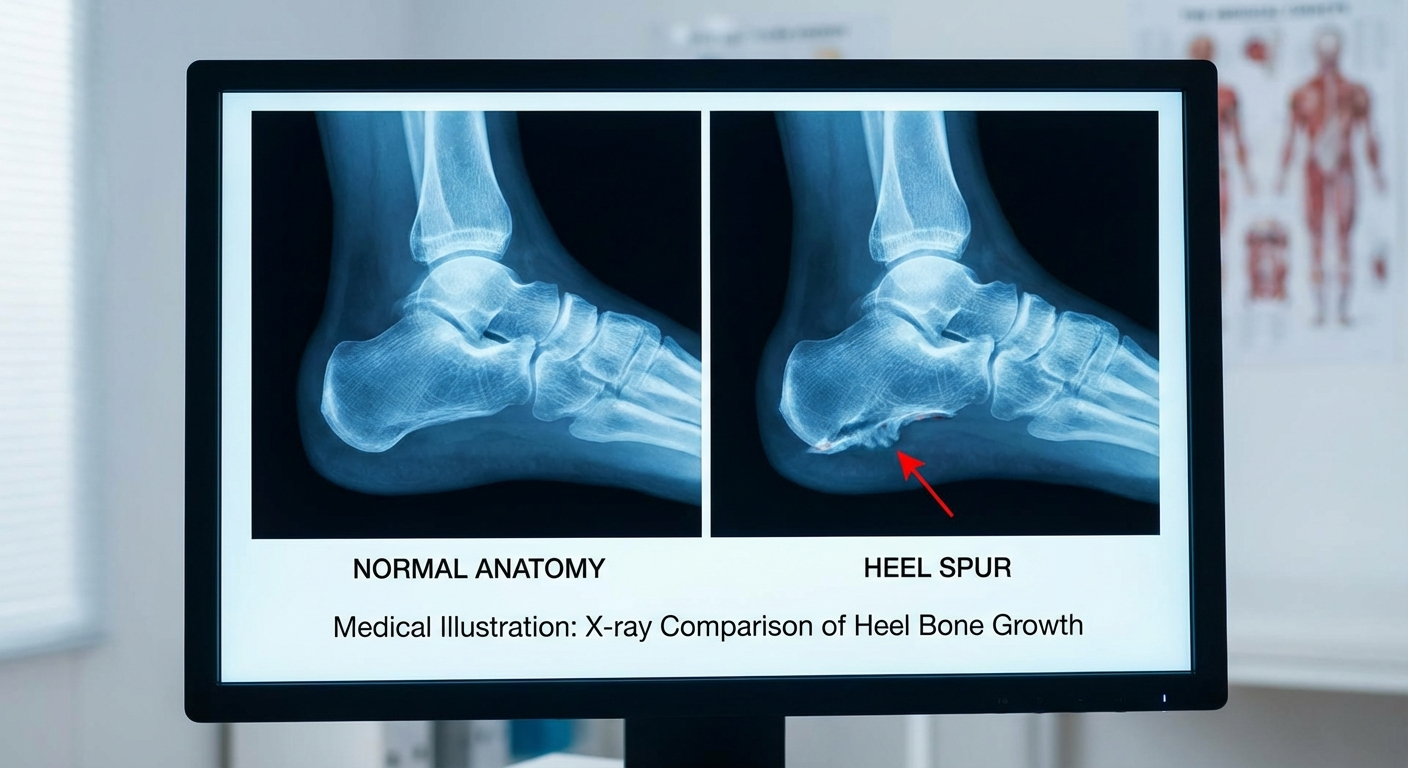

A heel spur is a structural, bony abnormality. It is a physical calcium deposit on the bone that can be seen on X-ray. The spur itself is often a secondary consequence of chronic plantar fasciitis rather than an independent condition.

X-ray (radiograph) — The primary diagnostic tool. A lateral foot X-ray will clearly show the bony protrusion extending from the calcaneus. Spurs can range from a few millimeters to over a centimeter in length.

It is critical to understand that the presence of a heel spur on X-ray does not mean it is causing your pain. Your clinician must correlate the imaging findings with your symptoms, physical examination, and clinical history to determine the true source of your heel pain.